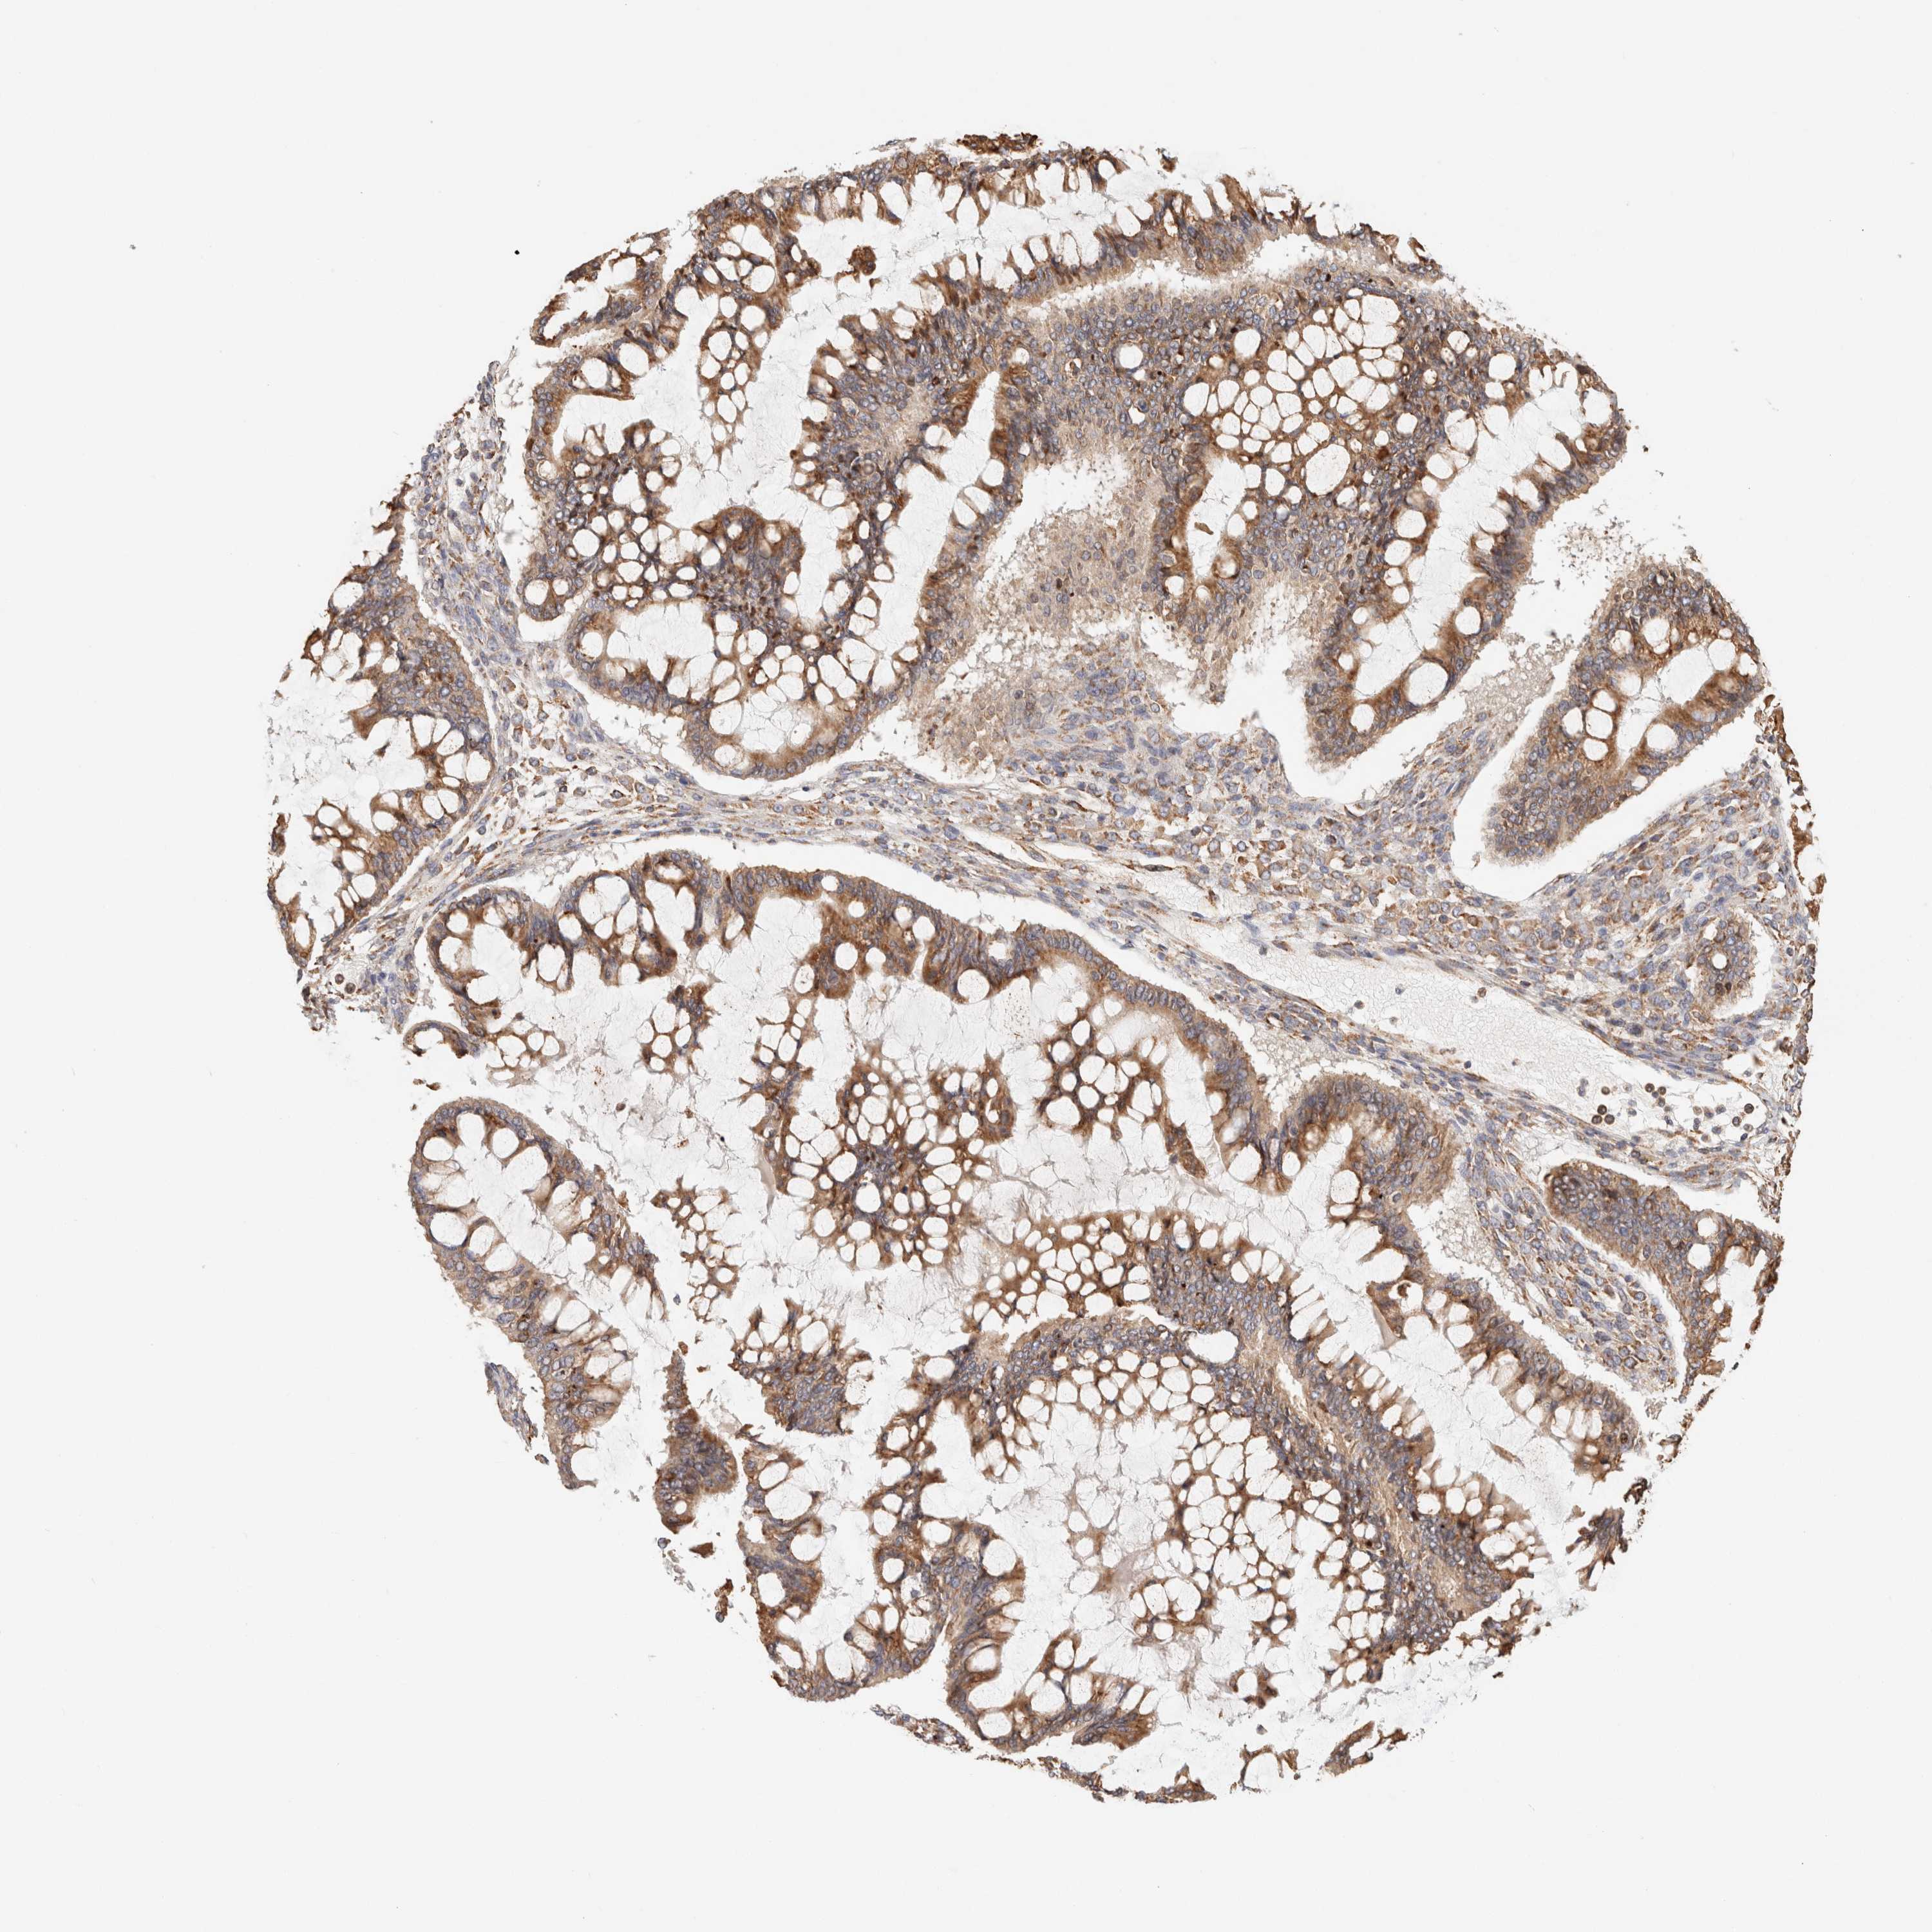

OVARIAN CANCER - Protein expressioni

A mouse-over function shows sample information and annotation data. Click on an image to view it in a full screen mode. Samples can be filtered based on level of antibody staining by selecting one or several of the following categories: high, medium, low and not detected. The assay and annotation is described here.

Note that samples used for immunohistochemistry by the Human Protein Atlas do not correspond to samples in the TCGA dataset.

Antibody stainingi

Antibody staining in the annotated cell types in the current human tissue is reported as not detected, low, medium, or high, based on conventional immunohistochemistry profiling in selected tissues. This score is based on the combination of the staining intensity and fraction of stained cells.

Each image is clickable and will lead to virtual microscopy that enables deeper exploration of all samples and also displays staining intensity scores, fraction scores and subcellular localization as well as patient and tissue information for each sample.

Antibody HPA007641

Antibody CAB022464

Cystadenocarcinoma, serous, NOS

Carcinoma, endometroid

Cystadenocarcinoma, mucinous, NOS

Carcinoma, NOS